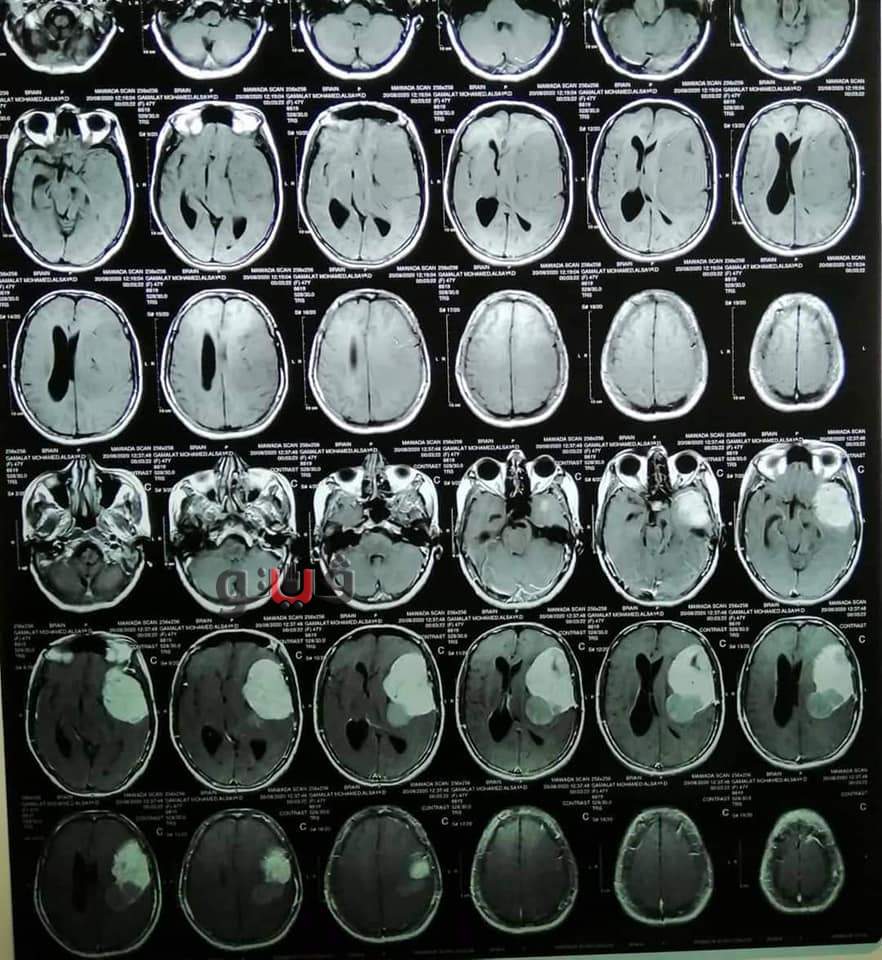

وأوضح الدكتور حسام النعمانى أستاذ ورئيس قسم جراحة المخ والأعصاب ورئيس الفريق الجراحى أن المريضة حضرت إلى عيادة جراحة المخ والأعصاب بالمستشفيات الجامعية تشكو من عدم الإتزان و بطء شديد بالكلام وصعوبة الحركة وبعد عمل الفحوصات الطبية المختلفة من رنين مغناطيسي وأشعة مقطعية وتحاليل أنسجة، تبين وجود ورم خبيث علي جدار المخ أثر على الإتزان والكلام و الحركة، على الفور تم تجهيز المريضة لإجراء الجراحة وتم إستئصال كامل للورم الخبيث بواسطة الميكروسكوب الجراحى، و المريضة حاليا بحالة جيدة بدون أى آثار جانبية، و يوجد تحسن بصورة كبيرة في الكلام والحركة.

وأشار الدكتور محمد الصاوى المدير التنفيذى للمستشفيات الجامعية إلى أنه تم إجراء الجراحة بإستخدام الميكروسكوب الجراحى لدقته العالية في مثل هذا النوع من الجراحات فهو يعطى أفضل نتائج ويساعد في الحفاظ على أنسجة المخ.